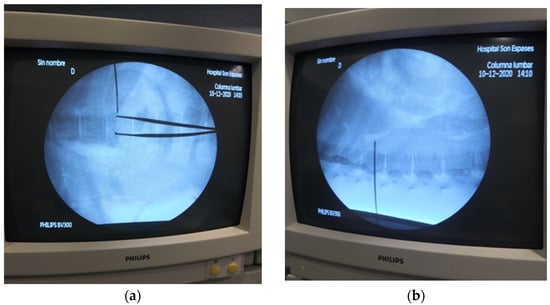

2.2. Preliminary Anatomical Description and Fluoroscopic Technique Development

3.1. Preliminary Anatomical Description and Fluoroscopic Technique Development